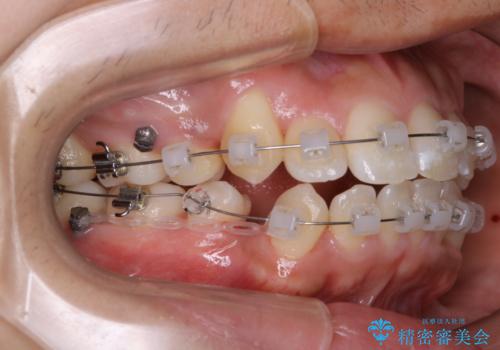

- 矯正装置

- クリア装置

親知らずと、前から4番目の歯を抜歯してワイヤー装置による矯正治療を行いました。

人前に出ることが多いため、当初は目立たない装置をご希望されていましたが、歯の移動距離が大きいため効率よく歯を動かせる表側の装置での治療をお勧めしました。すれ違ってしまっていた奥歯もしっかり治すことができました。